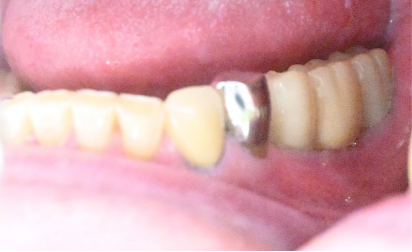

男性 Kさん 60代 (インプラント)

主訴

右下に1本の義歯を入れていたが、インプラントにしたい。

治療内容

インプラントを埋入しました。

所感

2026年2月9日にインプラント埋入手術をし、5月1日に最終的な被せ物を入れました。ブリッジや義歯は、歯がないところに掛かる力を、他の歯が支えることになります。インプラントは、他の歯に負担をかけることはありません。一本欠損になってしまったときは、1本だけインプラントを入れて、他の歯を護り、それ以上歯を失わないことが大切になります。

インプラント:¥363,000(税込)

Before

After